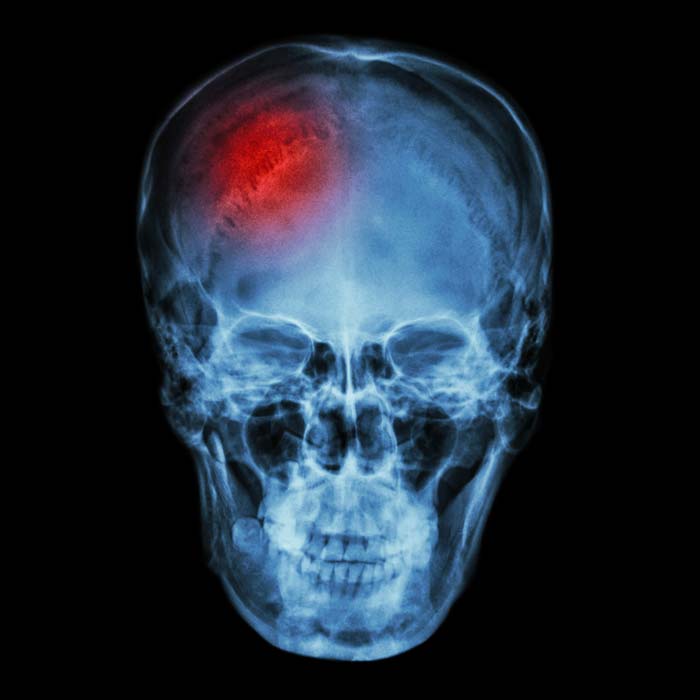

缺血性卒中的高血压反应

当大脑某个区域的血液供应被中断、减少或完全切断时,就会发生缺血性卒中。 当脑细胞耗尽氧气和营养物质、死亡、破裂并引发周围细胞的细胞死亡时,这种血液供应的损失会导致一连串的细胞死亡。 在初始治疗期间,每一秒都很重要,但即使在血液供应恢复后,危险还没有结束。

超过 80% 的缺血性卒中患者在卒中后数小时和数天内出现急性高血压。 这种血压升高可能是致命的,导致进一步的卒中、心脏病发作、动脉瘤和脑水肿。